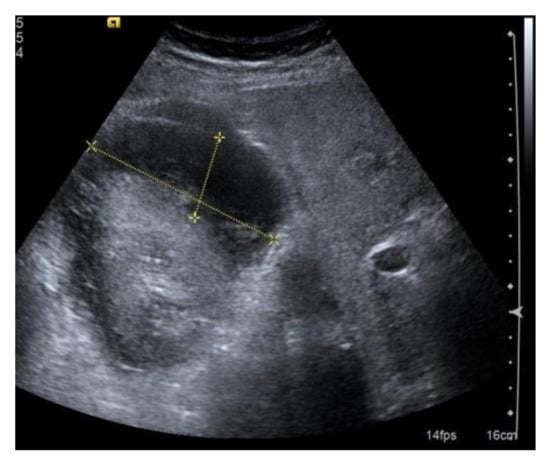

Although the ultrasound-guided execution of PRB after a thorough clinical assessment is relatively safe, adverse events are not infrequent and can be potentially fatal. Bleeding is certainly the most common complication. Hematoma (75% of complications) is generally well-recognizable with post-procedural ultrasound. It can be subcapsular, retroperitoneal or, rarely due to injury of the lumbar vessels (Figure 7). It has been described that the majority of patients with a detectable hematoma on the control ultrasound had minor or major complications (including bleeding requiring transfusion or radiologist intervention) in the few hours following the procedure. Hematoma is, therefore, a predictor of bleeding-related complications, but it seems as if there is no significant relationship between its size and the extent of bleeding [24,25]. Symptoms range from completely silent (small subcapsular hematomas) to hematuria, flank pain, anemia, and shock. The control of blood pressure and local compression may be sufficient in the management of subcapsular bleeding, while in the most severe cases, a super-selective angiography of the arterial vessels involved and subsequent embolization must be used [6]. Surgical treatment (which may include nephrectomy in fewer than 1% of complicated cases) is reserved for cases that cannot be treated intravascularly or cases of hemodynamic instability [7]. A special case of subcapsular bleeding is the page kidney, which is caused by the accumulation of blood in the perinephric or subcapsular space, resulting in extrinsic compression of the involved kidney, renal ischemia, activation of the renin–angiotensin–aldosterone system, and systemic hypertension. Arteriovenous fistula (AVF) is a relatively rare complication of kidney biopsy detectable with ECD, which is especially common in transplanted kidneys (described in up to 10% of biopsies). The treatment can be conservative or interventional in confirmed cases.

Figure 7.

Extensive post-bioptic subcapsular hematoma; the anecogenicity of the effusion indicates that the bleeding is recent, but it is not possible to obtain reliable information as to whether bleeding still exists. Size is an unreliable parameter in these cases. In the presence of post-biopsy hematoma, non-invasive dynamic contrast studies (CEUS or contrast-enhanced CT) can be very useful to evaluate a bleeding source and any rarer post-biopsy vascular complications.